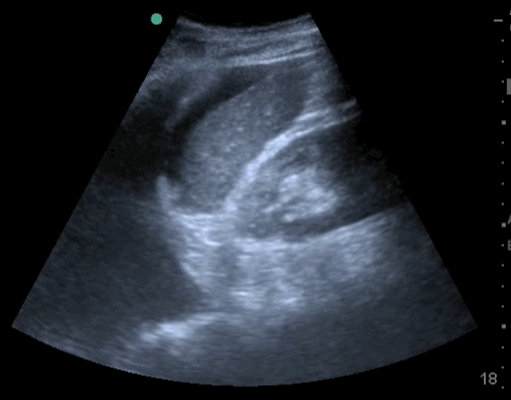

20_Abdomen_RUQ_Perihepatic

Free fluid – Hepatico-Diaphragmatic recess